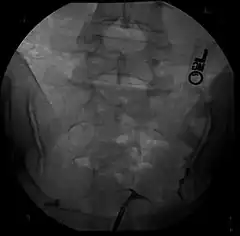

Image d’une hystérosalpingographie

- (Gynécologie) Radiographie de l’utérus et des trompes de Fallope.

Au cours d’une hystérosalpingographie, il est possible d’observer la présence de polypes ou de fibromes intracavitaires, ainsi que des accolements des faces utérines entre elles (on parle de synéchie).

— (François-Xavier Aubriot, Lucie Delaroche, Désir d’enfant - 100 conseils essentiels, 2017)L’hystérosalpingographie, également appelée hystérographie, est une procédure diagnostique couramment utilisée en gynécologie. Cette intervention médicale consiste à injecter un produit de contraste dans l’utérus et les trompes de Fallope d’une patiente, suivi de la réalisation d’images radiographiques pour visualiser ces organes.